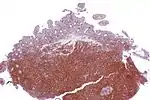

A defining characteristic of MCL is mutation and overexpression of cyclin D1, a cell cycle gene, that contributes to the abnormal proliferation of the malignant cells. MCL cells may also be resistant to drug-induced apoptosis, making them harder to cure with chemotherapy or radiation. Cells affected by MCL proliferate in a nodular or diffuse pattern with two main cytologic variants, typical or blastic. Typical cases are small to intermediate-sized cells with irregular nuclei. Blastic (aka blastoid) variants have intermediate to large-sized cells with finely dispersed chromatin, and are more aggressive in nature.[9] The tumor cells accumulate in the lymphoid system, including lymph nodes and the spleen, with non-useful cells eventually rendering the system dysfunctional. MCL may also replace normal cells in the bone marrow, which impairs normal blood cell production.

The immunophenotype profile consists of CD5+ (in about 80%),[10] CD10-/+, and it is usually CD5+ and CD10-.[11] CD20+, CD23-/+ (though plus in rare cases). Generally, cyclin D1 is expressed but it may not be required. Cyclin D1 negative mantle cell lymphoma can be diagnosed by detecting SOX11 marker. The workup for Mantle cell lymphoma is similar to the workup for many indolent lymphomas and certain aggressive lymphomas.